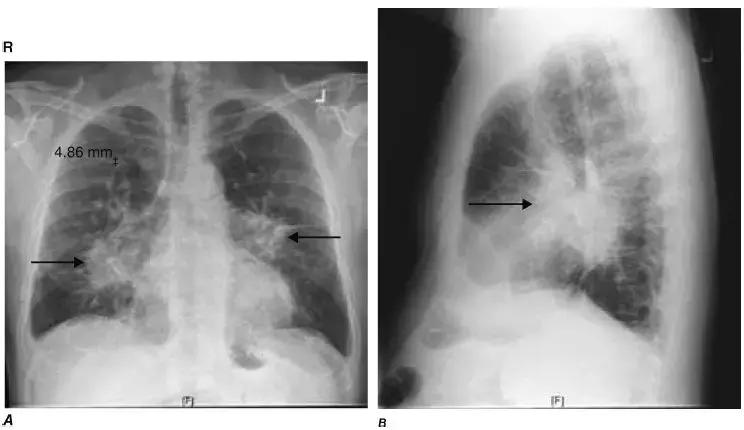

图4-23 Ⅱ期结节病胸片:A.正位胸片显示肺门淋巴结肿大(黑箭头)和肺实质改变;B.侧位片显示肺门淋巴结肿大(黑箭头)和肺实质改变